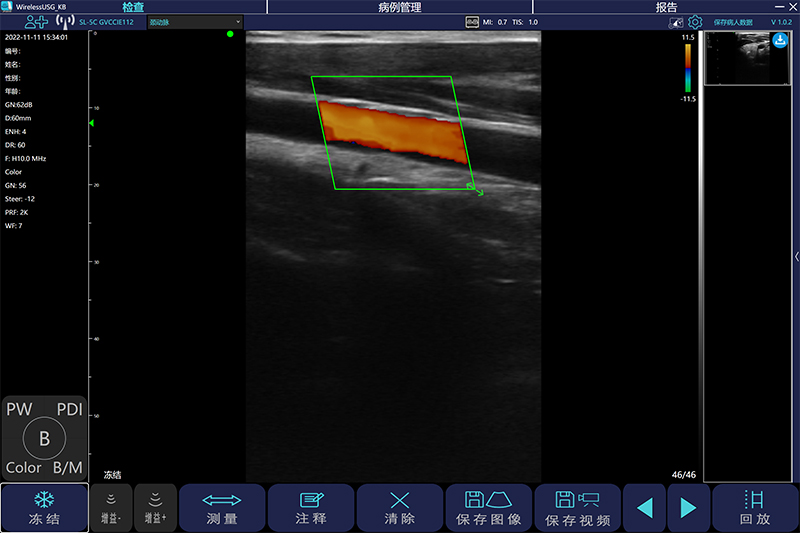

细节决定成败-------超声引导下的血管穿刺

http://www.dxy.cn/bbs/topic/30047605转载自丁香园我在危重版块混的时间也久了,承各位版主,战友看的起,发的帖子还算得到好评,自己也在危重版块学了很多知识。其实整个···

超声在血管外科中的应用

作者:杨宝钟[1]单位:北京中医药大学东方医院[1] 超声作为一种无创检查方法,已经广泛用于血管外科。它不仅可以显示病变部位,还可以显示病变范围,病变与周围器官的关系、···

黑白B超与彩色B超的区别有哪些呢?

大家所听说的黑白B超、彩超是目前在医院中最广泛应用的,用于各个器官的检查等,那么黑白B超与彩色B超的区别有哪些呢?黑白B超是采用灰度调制显示声束扫描人体切面的声像图。···